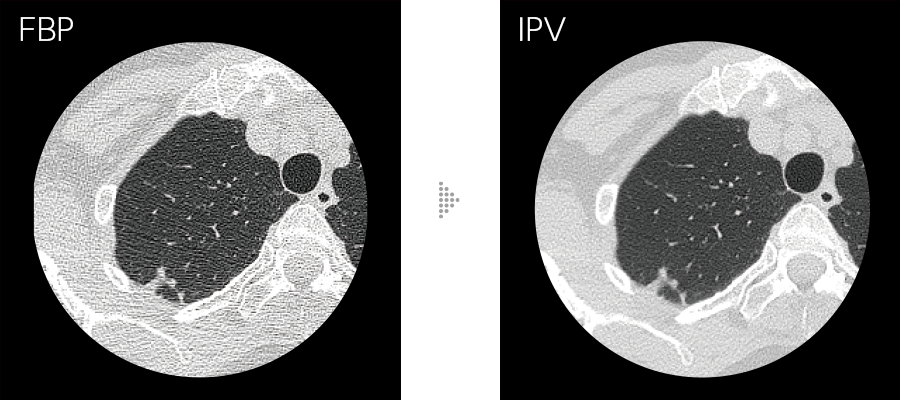

Our iterative reconstruction method, Intelli IPV, provides images that maintain their natural texture even at high noise reduction rates and their excellent visibility even at low doses, and does not require a dedicated operating room or additional hardware.

While adjusting the texture at a uniform ratio from high frequency to low frequency, the physical properties that affect visibility are made as close as FBP.